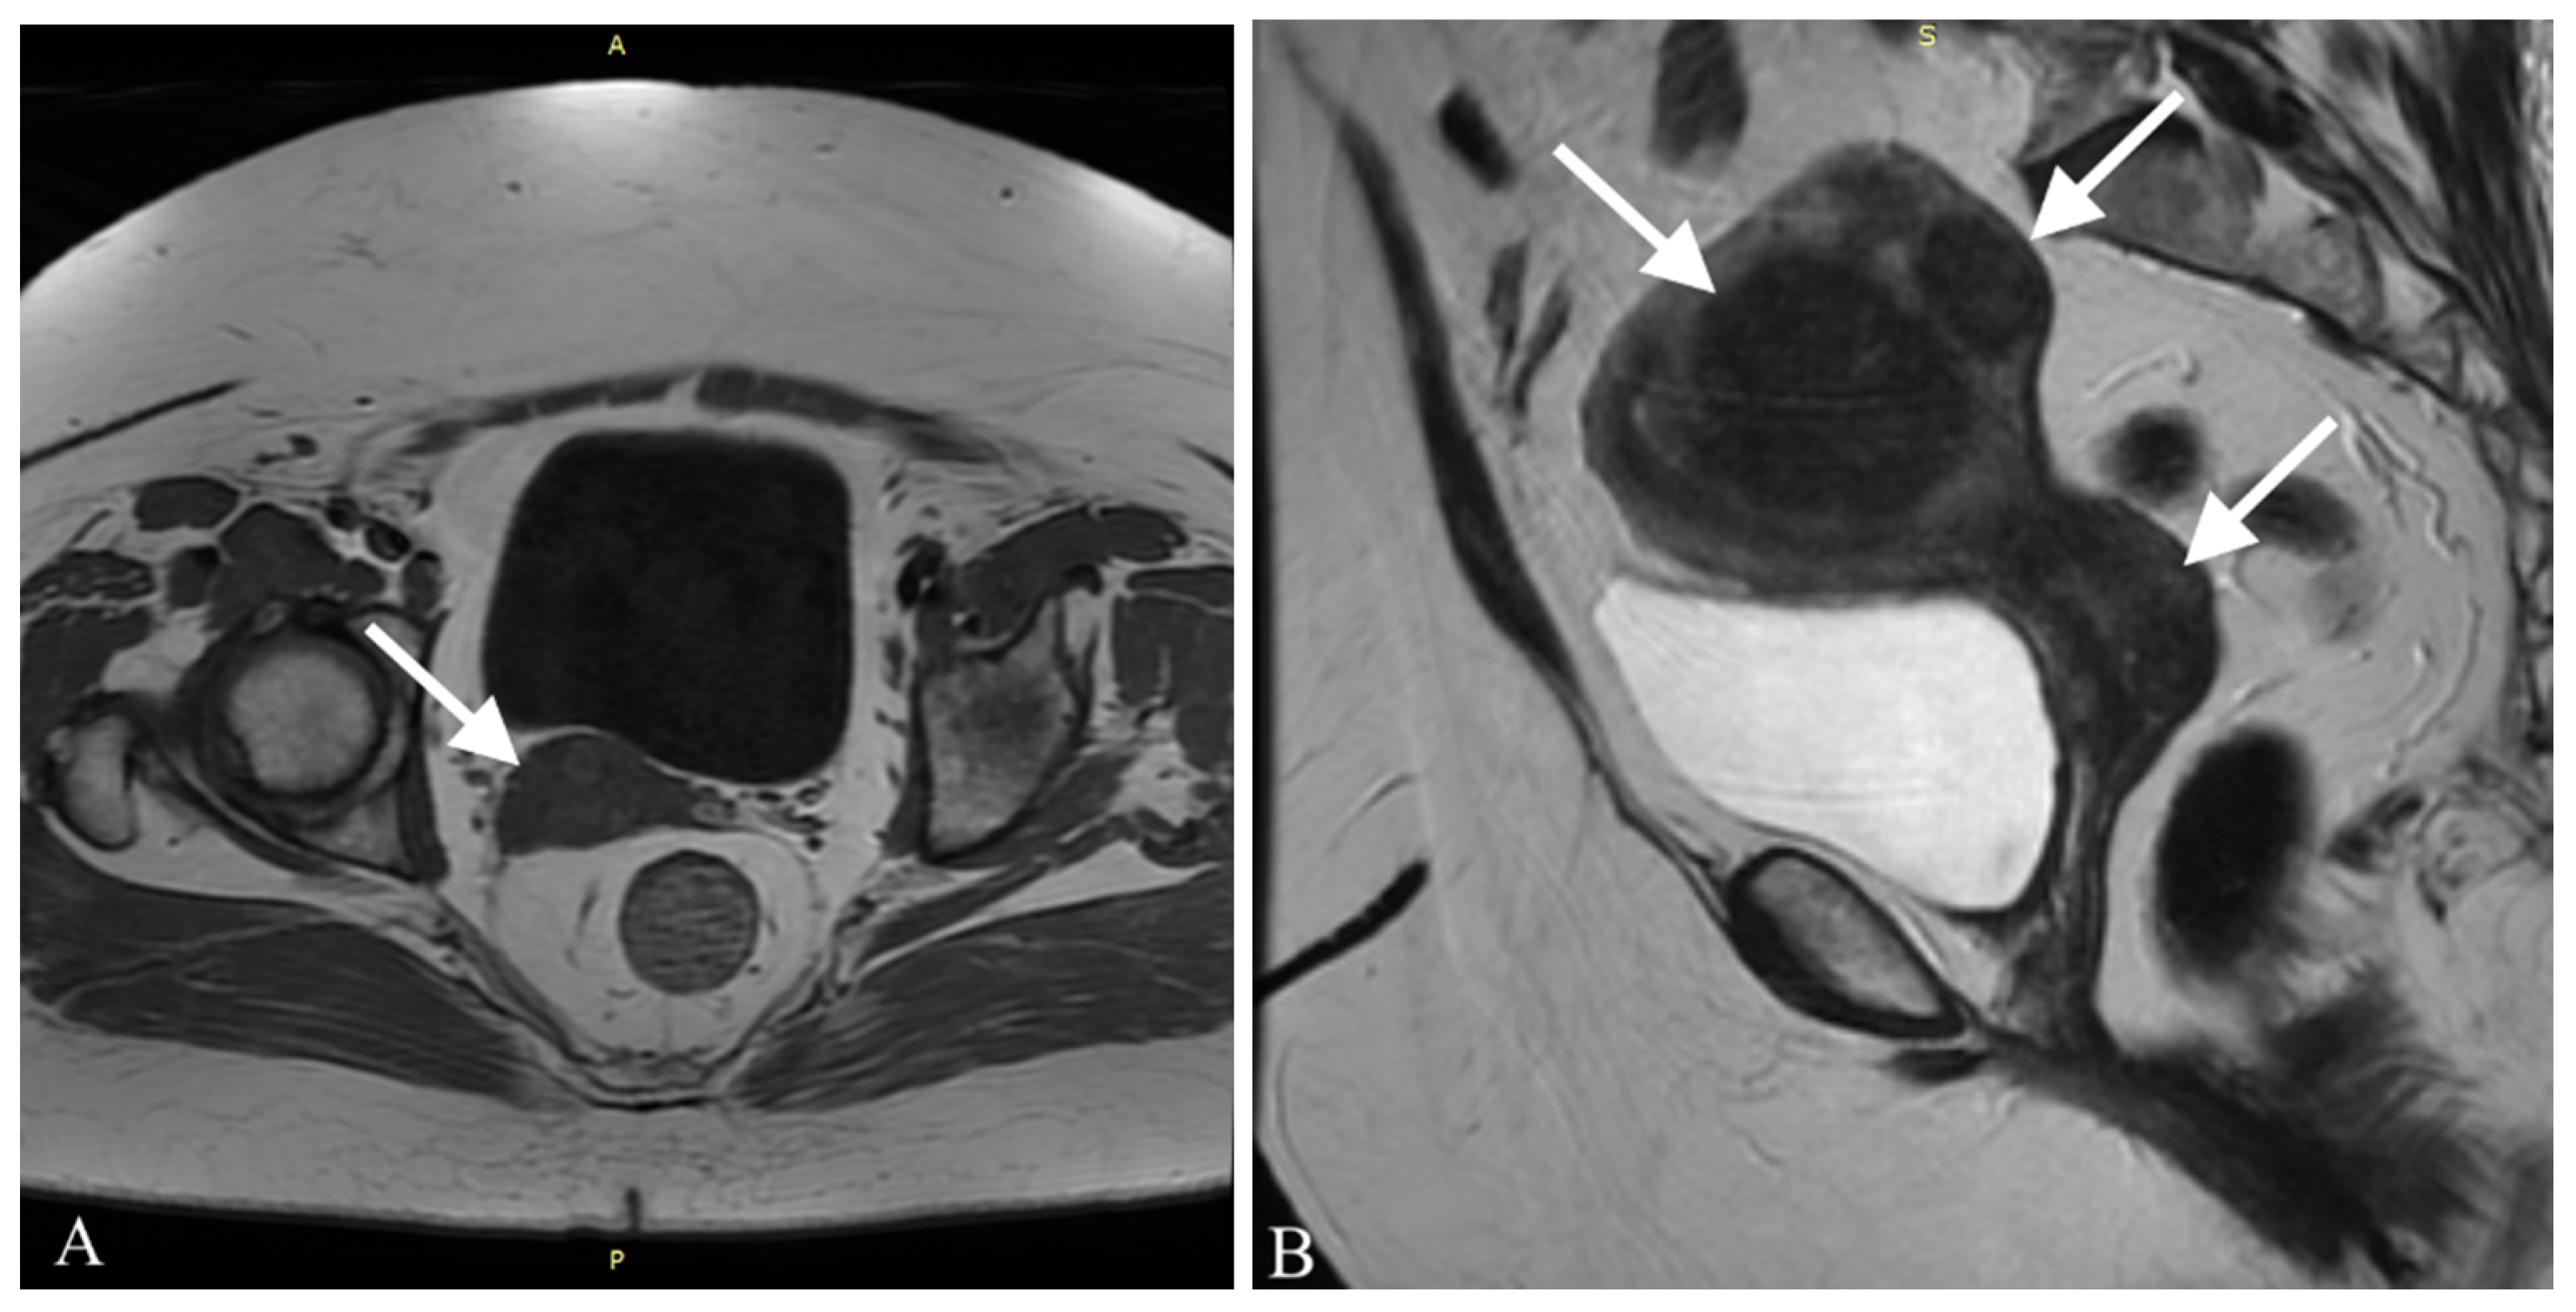

After the surgery, the patient was regularly monitored in the outpatient clinic in the first year once every 3 months and afterwards once every 6 months. Three months after the surgery, a cytological examination was performed and no irregularities were found. The patient showed no symptoms and reported no complaints. One year after the surgery a CT scan of the chest and MRI of the pelvis and abdomen were performed—with no signs of neoplasm whatsoever. A postoperative MRI of the pelvis is shown in Figure 3.

Figure 3. A postoperative MRI of the pelvis in axial projection, performed 18 months after the Wertheim–Meigs operation. A vaginal stump is visible. No signs of recurrence are present.